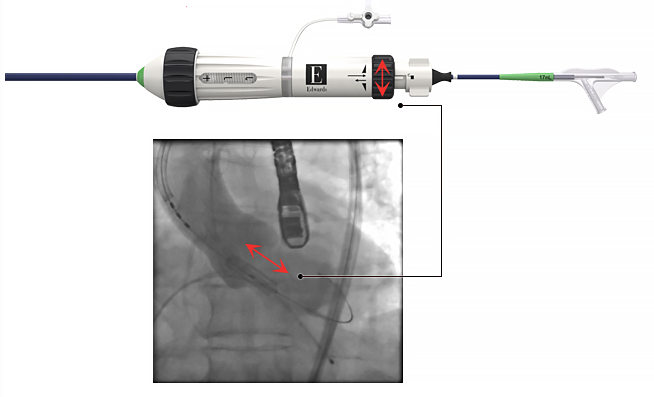

経カテーテル大動脈弁留置術 「 TAVI (タビ)」 は、カテーテルと呼ばれる医療用の管を用いて大動脈弁を人工弁に置き換える治療法で、従来の開胸大動脈弁置換術よりも低侵襲であり、手術が困難と判断された高齢の方でも可能な大動脈弁狭窄症の新しい治療方法となります。